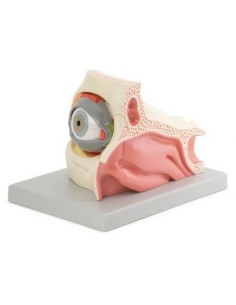

3B Scientific, modello anatomico di occhio nella cavità oculare ingrandito di 3 volte,...

Erler Zimmer, modello anatomico di occhio nella cavità oculare con palpebra F160

Erler Zimmer, modello anatomico di occhio con orbita e palpebra, ingrandito di 6 volte...